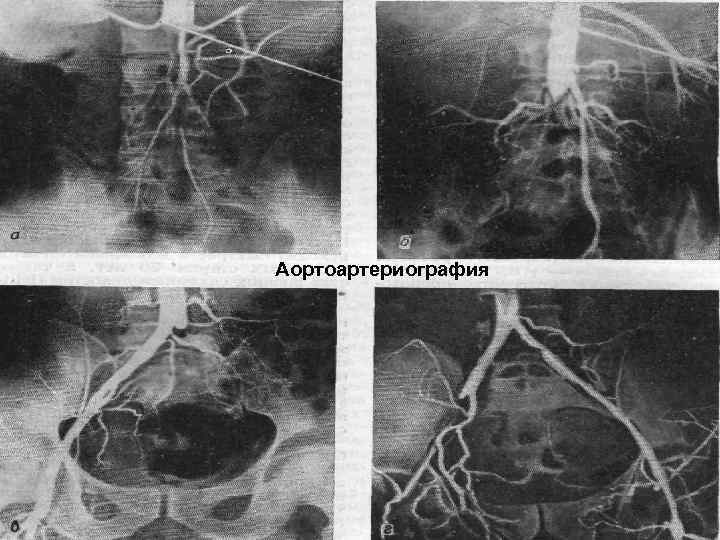

Диагностика n определение регионарного артериального давления, n реография, n допплерография, n радионуклидная ангиография, n компьютерная томография n рентгеноконтрастная ангиография и аортография. 57

Аортоартериография 60